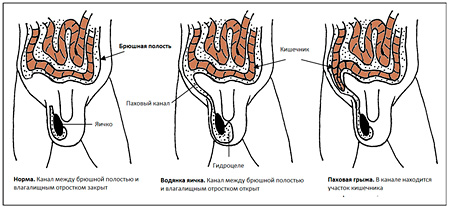

Hydrocele és lágyéksérv

Ez azzal jellemezve kommunikáló hydrocele visszatartó összekötő csatorna között egy tunica vaginalis és a has. Ha a csatorna elég széles, a hatóságok bele. található a hasüregben. Bél van egy viszonylag nagy a mobilitás és könnyen lehet mozgatni egy nyitott csatornát, amint az a harmadik diagramon. Így egy lágyéksérv.

Ábra. Hydrocele és lágyéksérv.

A bélben is található elején a csatorna, és leesik a here. A sérv veszélyes lehet, és tele van súlyos szövődmények.